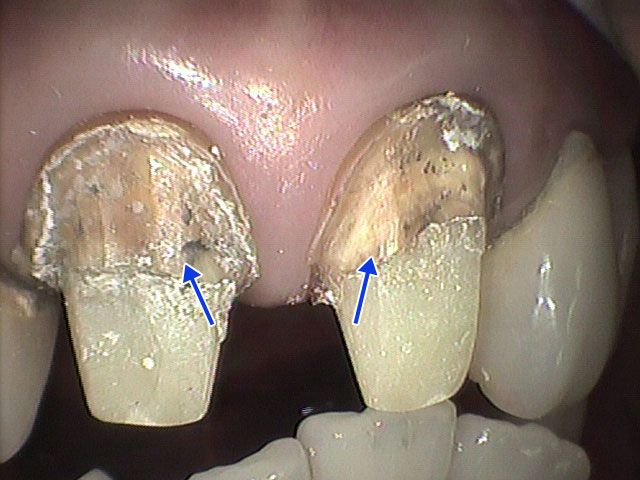

4.問題のある自費補綴の症例

以下に示す例は自費治療としては少々、疑問の残る症例です。自費治療は保険診療とは次元の異なるハイレベルの品質が求められています。定型的な細工仕事ですますのではなく、自費治療に相応しい臨床技術を発揮する必要があります。

(Video-1) 支台歯(矢印)から検出された細菌